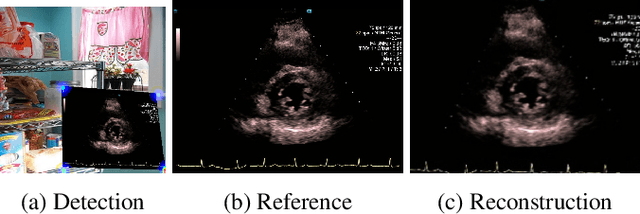

Abstract:Ultrasound (US) machines display images on a built-in monitor, but routine transfer to hospital systems relies on DICOM. We propose a self-supervised pipeline to extract the US image from a photograph of the monitor. This removes the DICOM bottleneck and enables rapid testing and prototyping of new algorithms. In a proof-of-concept study, the rectified images retained enough visual fidelity to classify cardiac views with a balanced accuracy of 0.79 with respect to the native DICOMs.